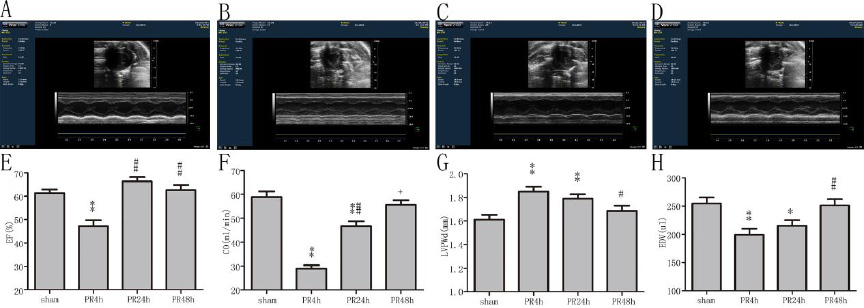

PR 4 h组大鼠EF值较sham组显著下降(P < 0.01,图 1),PR 24 h及PR 48 h组大鼠EF值与sham组比较差异无统计学意义(均P > 0.05);PR 4 h及PR 24 h组大鼠CO较sham组均显著下降(均P < 0.01),且PR 24 h组高于PR 4 h组(P < 0.01),但PR 48 h组与sham组比较差异无统计学意义(P > 0.05);PR 4 h及PR 24 h组大鼠LVPWd较sham组均显著增厚(均P < 0.01),PR 48 h组与sham组比较差异无统计学意义(P > 0.05);PR 4 h及PR 24 h组大鼠EDV较sham组均显著变小(均P < 0.05),PR 48 h组与sham组比较差异无统计学意义(P > 0.05)。

| A:sham组(n=6);B:PR 4 h组(n=9);C:PR 24 h组(n=9);D:PR 48 h组(n=7);E:EF值的比较;F:CO的比较;G:LVPWd的比较;H:EDV的比较;与sham组比较,aP < 0.05和bP < 0.01;与PR 4 h组比较,cP < 0.05和dP < 0.01;与PR 24 h组比较,eP < 0.05 图 1 各组动物射血分数、心输出量、舒张期左室后壁和舒张末左室容量的比较 Figure 1 Comparison of EF, CO, LVPWd and EDV among groups |

PRMD在ROSC后数分钟即可发生,左室收缩舒张功能均受损,可引起心源性休克进而导致多脏器功能衰竭,这种早期发生的、严重的心功能障碍,可在ROSC后数天至数周内完全恢复[9-10]。Kern等[11]发现在猪的CA模型中,复苏后数小时内EF值、每搏输出量(SV)明显下降,但心功能在复苏后48 h可完全恢复。Laurent等[12]研究显示,对于CA复苏成功的患者,血流动力学不稳定主要表现在ROSC后4~7 h内,表现为心输出量明显降低,而在ROSC 24 h后患者的CO会迅速升高,72 h左右可恢复至正常水平。本研究的6 min CA模型中,ROSC 4 h时心脏收缩舒张功能均明显下降,但48 h时可恢复至正常水平,这也与之前研究中PRMD特点相符[9-12]。这种暂时性心功能障碍提示CA/ROSC后心肌损伤非持续性的损伤或梗死。